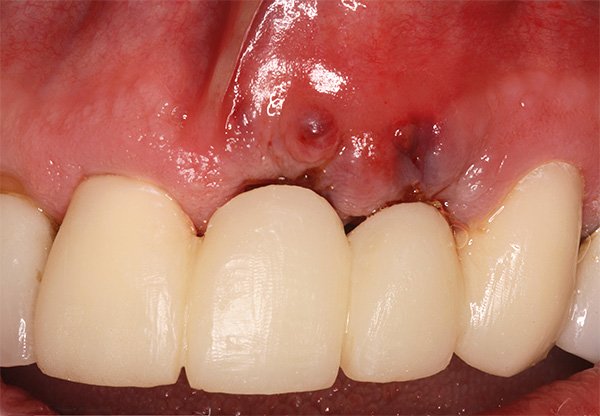

Отторжение зубного импланта может проявляться через боль, отек и покраснение в области имплантации. Пациенты могут испытывать дискомфорт при жевании или замечать подвижность импланта. Основной причиной отторжения является инфекция, возникающая из-за недостаточной гигиены или несоблюдения рекомендаций врача. Также важны индивидуальные особенности, такие как аллергические реакции или аутоиммунные заболевания. Неправильное размещение импланта и недостаточная остеоинтеграция могут привести к неудаче процедуры. Врачи подчеркивают необходимость тщательного обследования и соблюдения рекомендаций для минимизации рисков.

Эксперты в области стоматологии отмечают, что отторжение зубного импланта может быть вызвано несколькими ключевыми факторами. Основные признаки, указывающие на возможные проблемы, включают боль, отек и подвижность импланта. Эти симптомы могут свидетельствовать о воспалении или инфекции в области установки. Причинами отторжения могут быть как недостаточная остеоинтеграция, так и аллергические реакции на материалы импланта. Неправильный уход за полостью рта, а также наличие системных заболеваний, таких как диабет, также могут негативно сказаться на успешности имплантации. Важно, чтобы пациенты следовали рекомендациям стоматолога и регулярно проходили контрольные осмотры для предотвращения осложнений.

Отторжение зубного импланта — это тема, которая вызывает много обсуждений среди пациентов и стоматологов. Многие люди отмечают, что основными признаками проблемы являются боль, отек и дискомфорт в области импланта. Некоторые пациенты сообщают о том, что чувствуют, как имплант «шатается», что может свидетельствовать о недостаточной интеграции с костной тканью. Причины отторжения могут быть разнообразными: от инфекций и аллергических реакций до недостаточной гигиены полости рта и неправильного выбора материала импланта. Также важно учитывать индивидуальные особенности организма, такие как наличие хронических заболеваний или курение, которые могут негативно сказаться на процессе заживления. Многие стоматологи подчеркивают важность тщательной диагностики и подготовки перед установкой импланта, чтобы минимизировать риск отторжения и обеспечить долгосрочный успех лечения.

| Боль, отек, покраснение десен вокруг имплантата | Инфекция, недостаточная остеоинтеграция, перегрузка имплантата | Визуальный осмотр, рентгенография, анализ крови |

| Гнойные выделения из десен вокруг имплантата | Инфекция, периимплантит | Визуальный осмотр, микробиологический анализ |